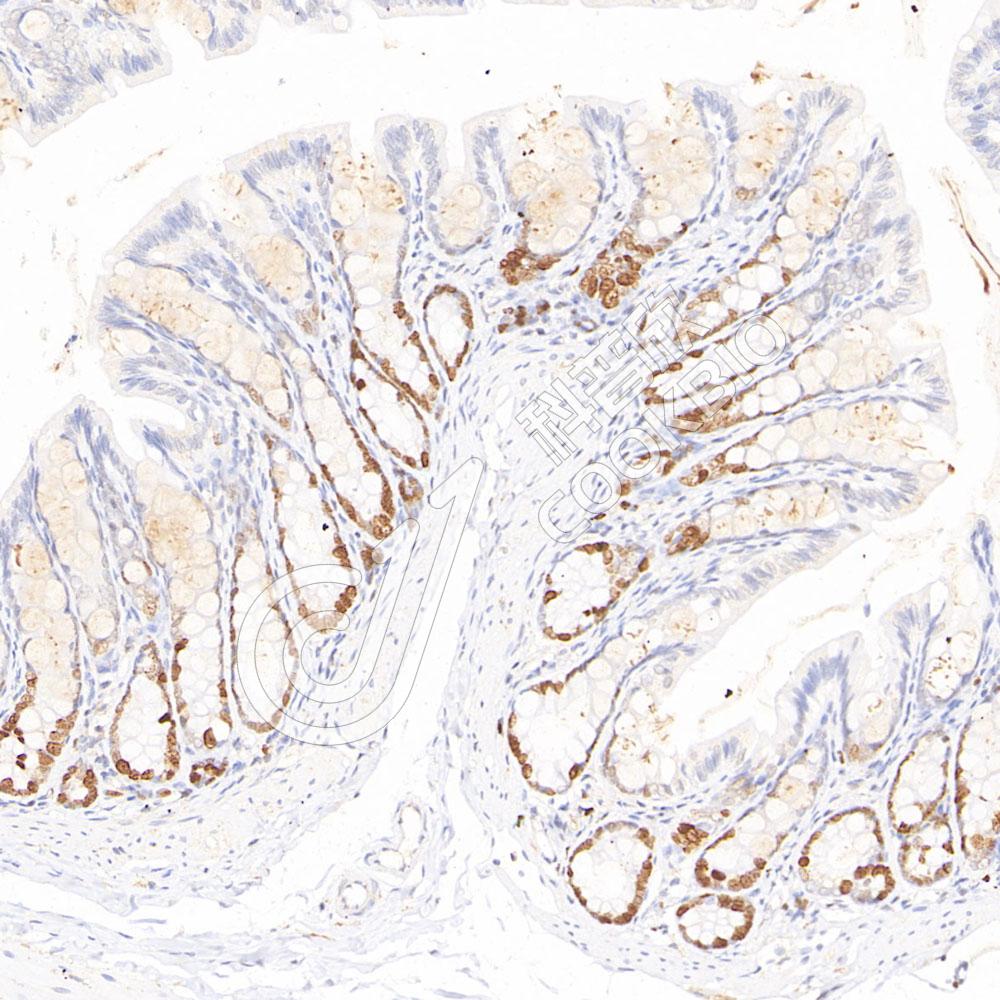

IHC检测Ki67蛋白(货号 K5453423).

样品: 小鼠结肠, 4%多聚甲醛 (货号KSG1101) 固定12-24小时.

抗原修复: 柠檬酸抗原修复液(干粉, pH 6.0) (KSG1201), 高压锅均匀喷气计时2分钟.

—抗: 1: 800稀释, 4℃ 孵育过夜.

二抗: S-vision免疫组化多聚二抗(山羊抗小鼠), 即用型(货号KB3903), 室温孵育20分钟.